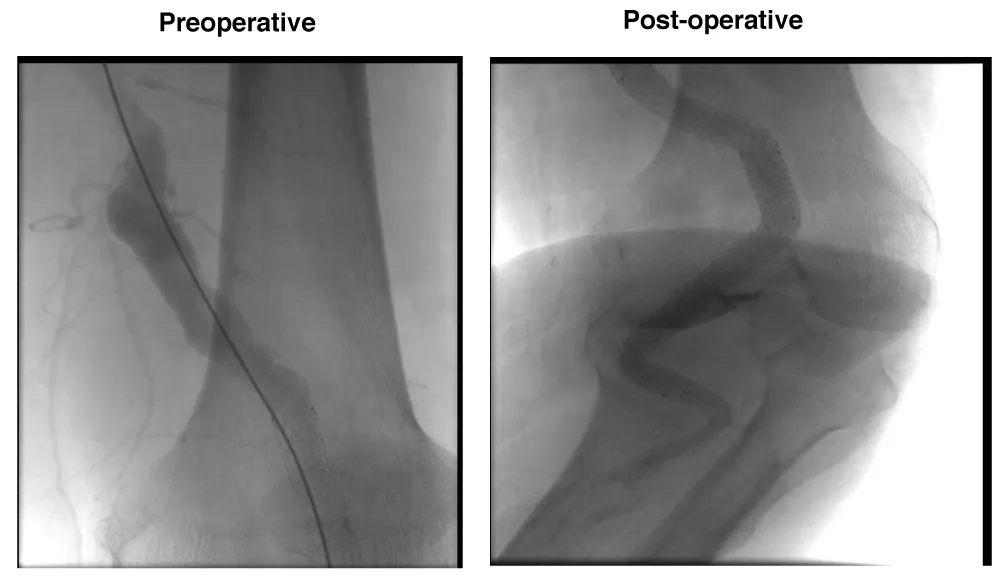

A male patient, 81 years, active smoker, with arterial hypertension and diabetes was admitted with right Lower limb distal microembolization, due to a 24 mm popliteal arterial aneurysm. The patient was submitted to endovascular surgery with the popliteal implant of endoprosthesis Wrapsody® 10x125 mm at distal neck, followed by an implant of Wrapsody 10x125 mm and Wrapsody 12x80 mm at proximal neck, followed by catheter balloon dilatation. (Figure 4).

Figure 4: Repair of a 24 mm popliteal artery aneurysm in an 81-year-old male with distal embolization: Preoperative image highlights microembolization signs and aneurysm. Postoperative angiogram demonstrates successful repair using three Wrapsody® endoprostheses (10×125 mm, 10×125 mm, 12×80 mm) with full restoration of patency and distal flow.

The patient was discharged from the hospital first day post-operative with Rivaroxaban 20 mg/day and a 1-month follow-up showed endoprosthesis patency with complete resolution of the previous symptoms.